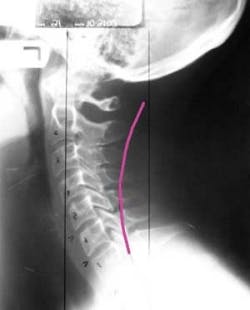

Radiograph taken of the author's spine in 2005. The pink line indicates where her vertebra should have lined up.

First, I sought the help of a chiropractor who obtained radiographs of my cervical spine. What we discovered shocked and alarmed me. I was already starting to lose the natural curvature of my spine and compromising nerves and disks, and I was only 20 years old.